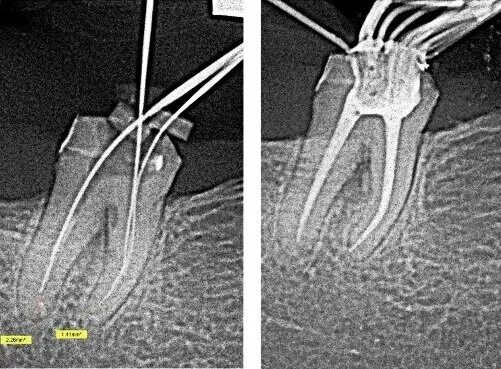

Удаление нервов в зубе и пломбирование